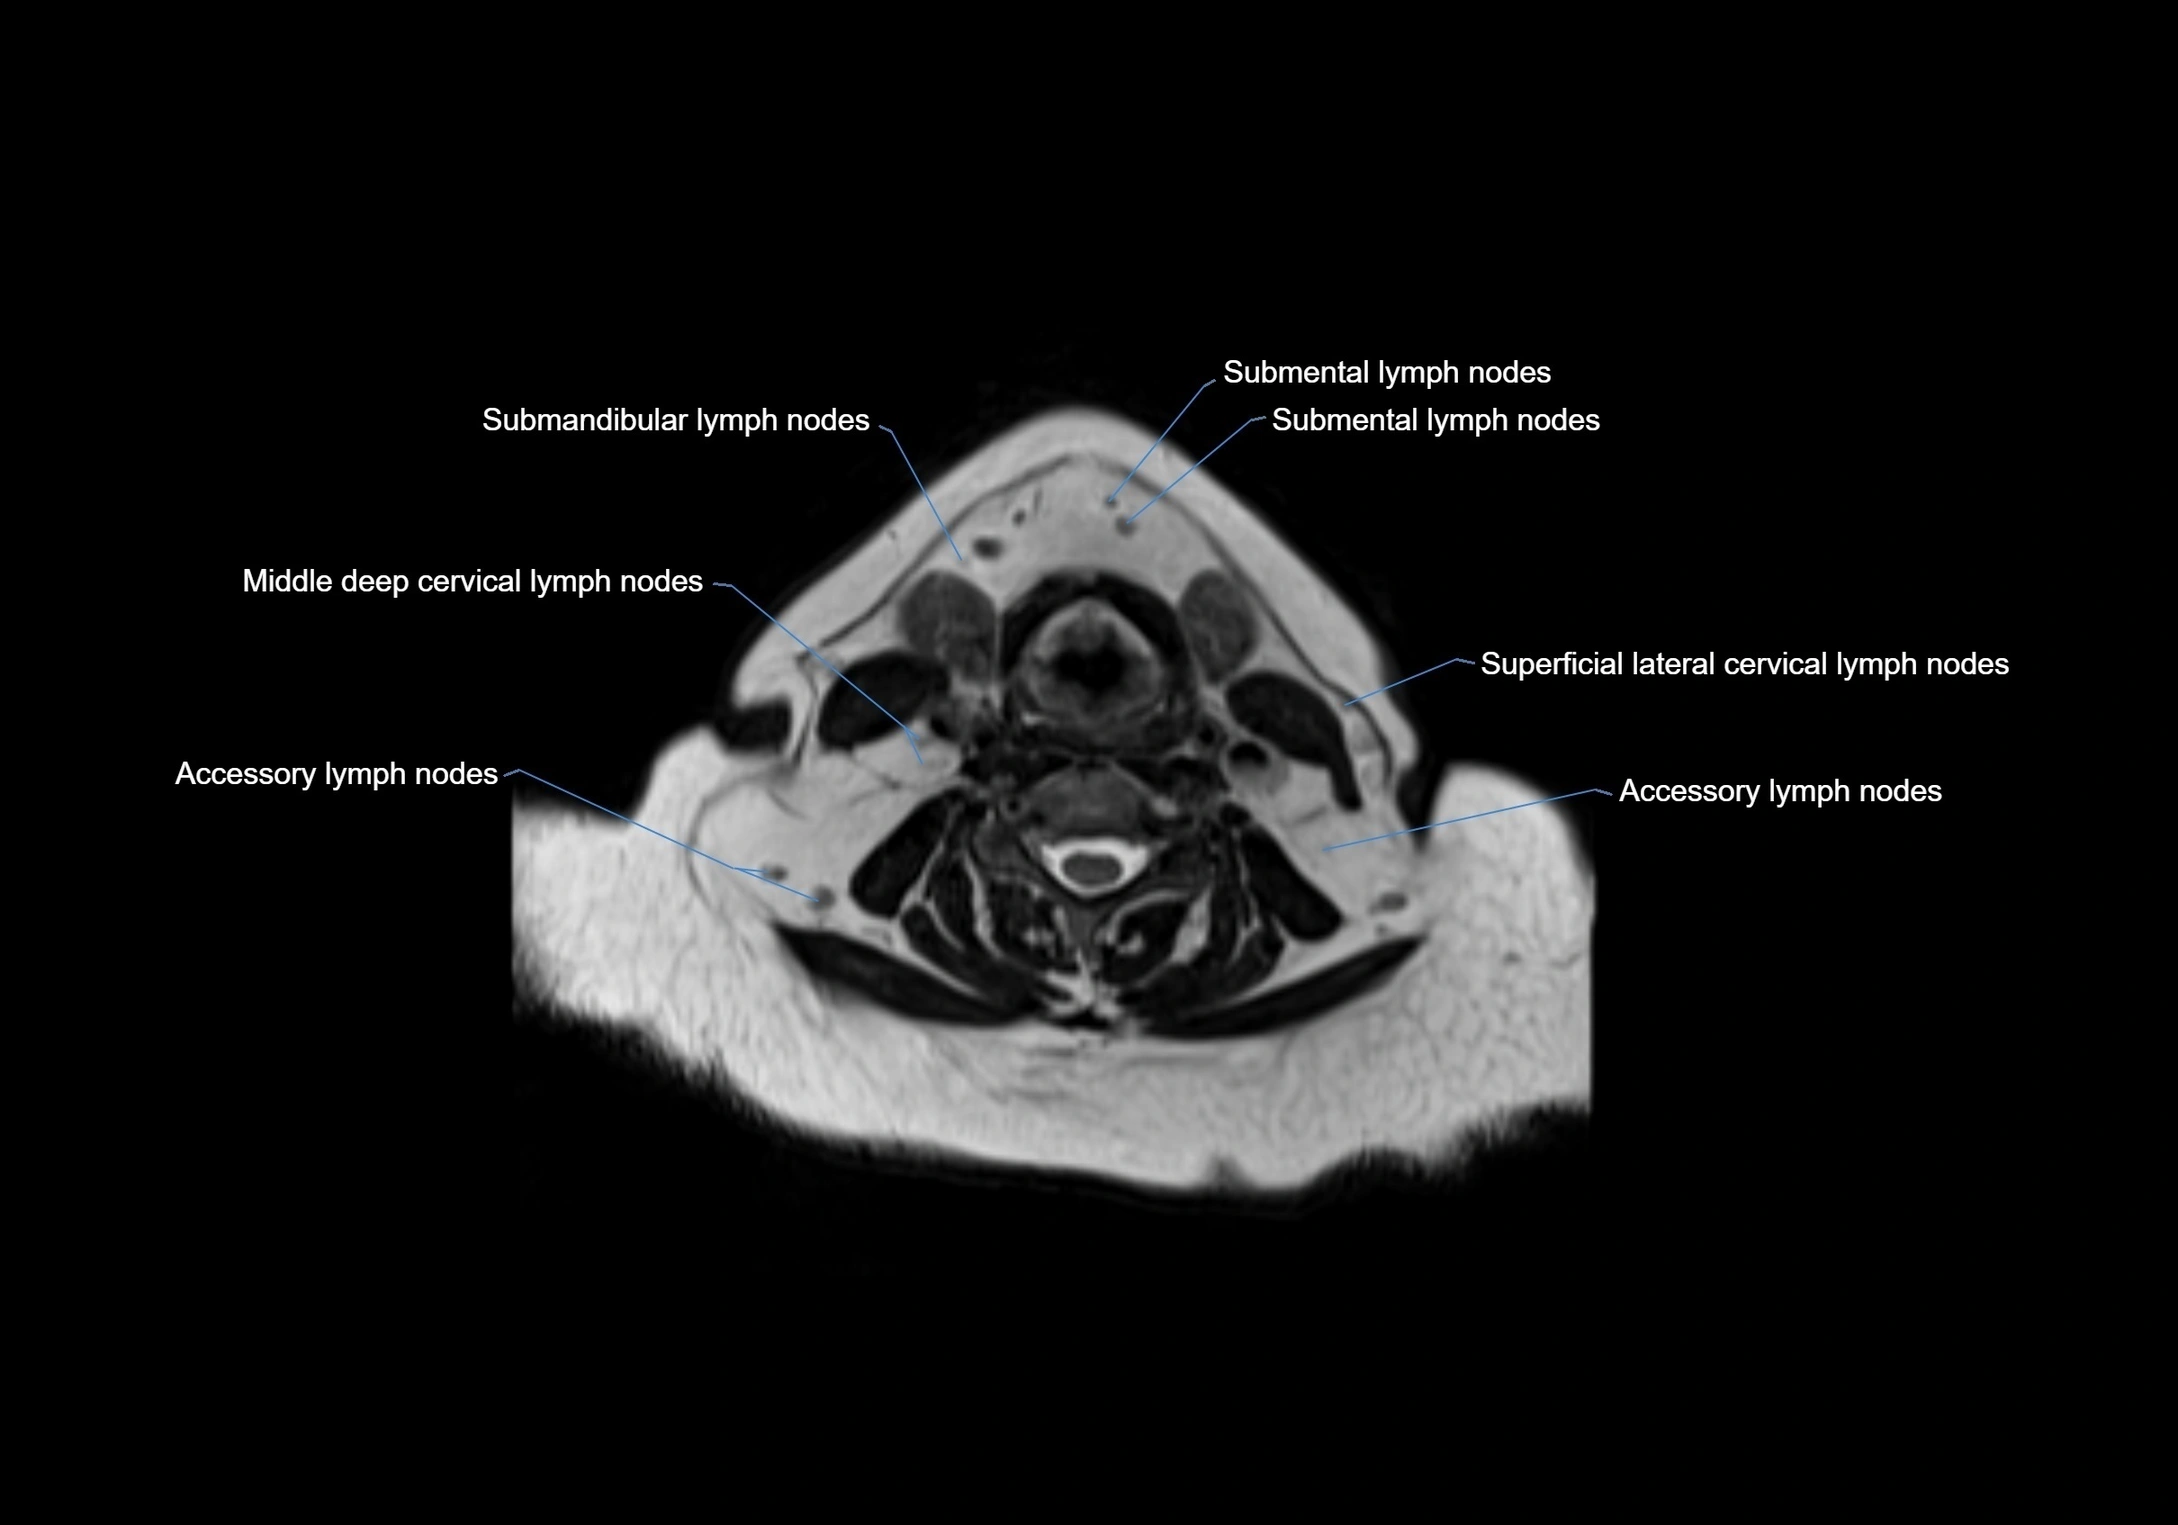

Accessory lymph nodes

Accessory lymph nodes are small, secondary lymph nodes located along the main facial and cervical lymphatic chains, often adjacent to primary lymph nodes, such as preauricular, submandibular, or occipital nodes. They are typically less than 5 mm in diameter, embedded within subcutaneous fat or connective tissue, and may be variable in number and location. These nodes provide additional filtration and immune surveillance for lymph collected from the face, scalp, and neck regions. Accessory lymph nodes are usually non-palpable in healthy individuals but may enlarge in response to infection, inflammation, or metastasis, making them clinically significant.

MRI images

image